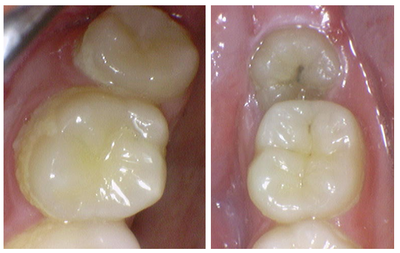

2024. 9 첫 내원 당시의 구강 내 DSLR 촬영 사진

누워있는 사랑니 주위로 약간의 잇몸 염증이 관찰되며,

치아에 초기 충치가 생긴 모습도 관찰됩니다.

우측 위 사랑니 부위 (좌측 사진) - 우측 아래 사랑니 부위(우측 사진)